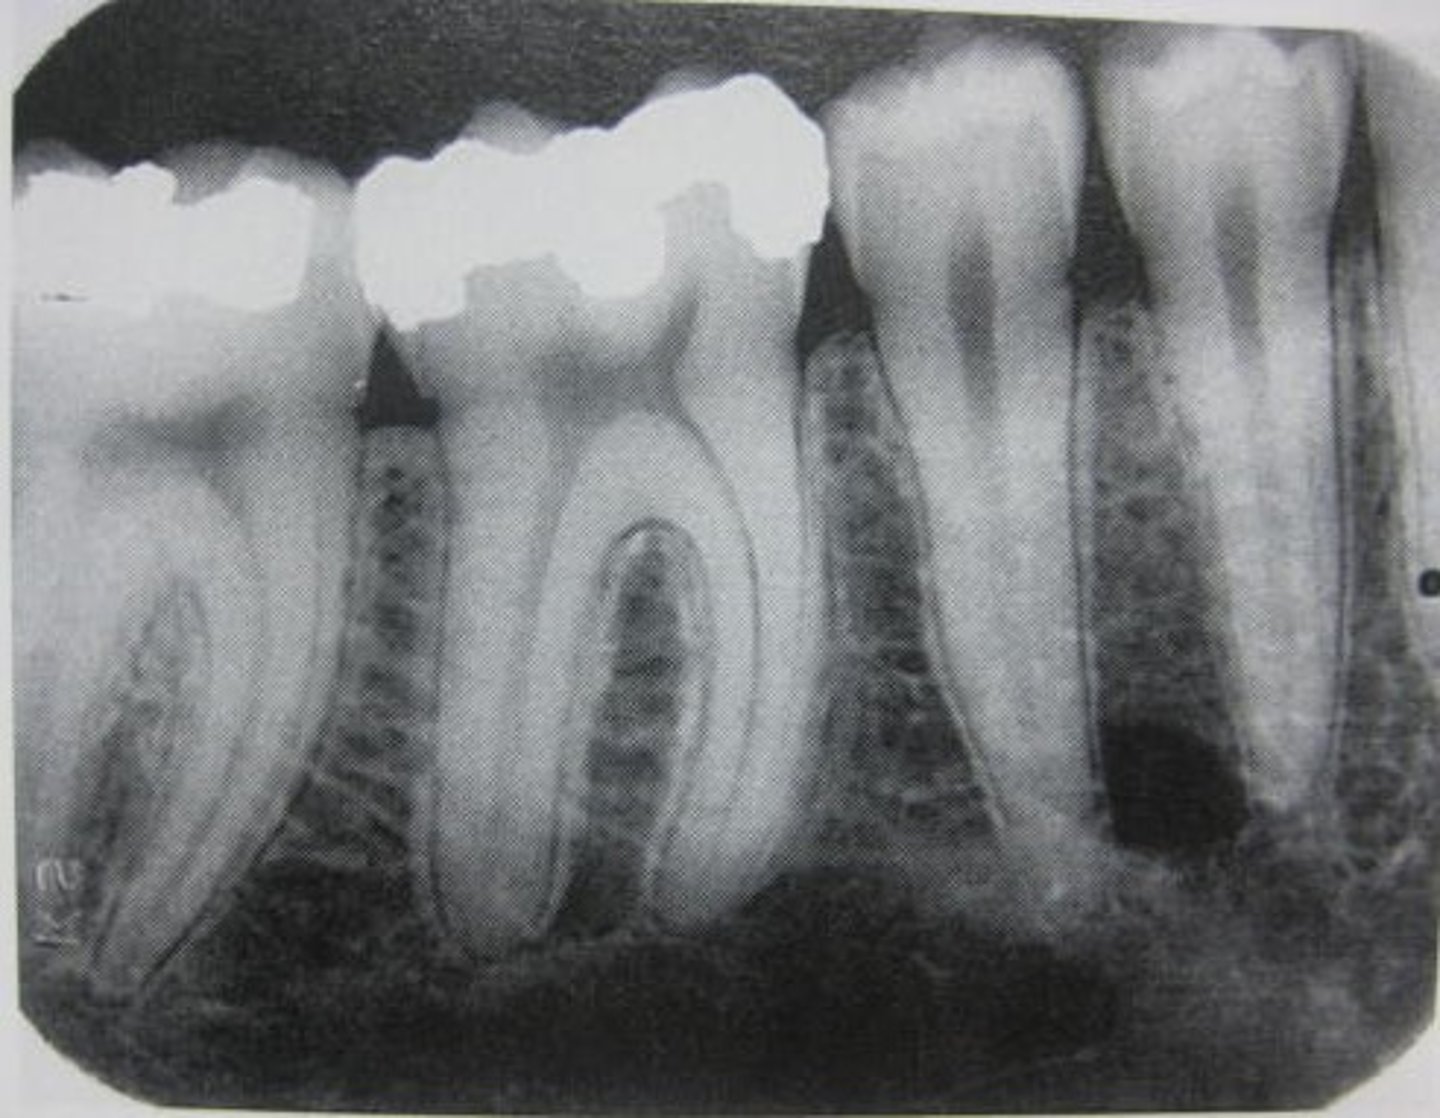

Periapical

"around the root" to see entire tooth and surrounding bone

Why do we take PAs?

show roots and surrounding bone